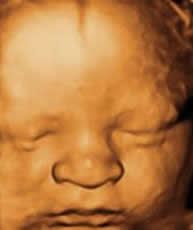

Obstetric Ultrasound for

• 4D Scan